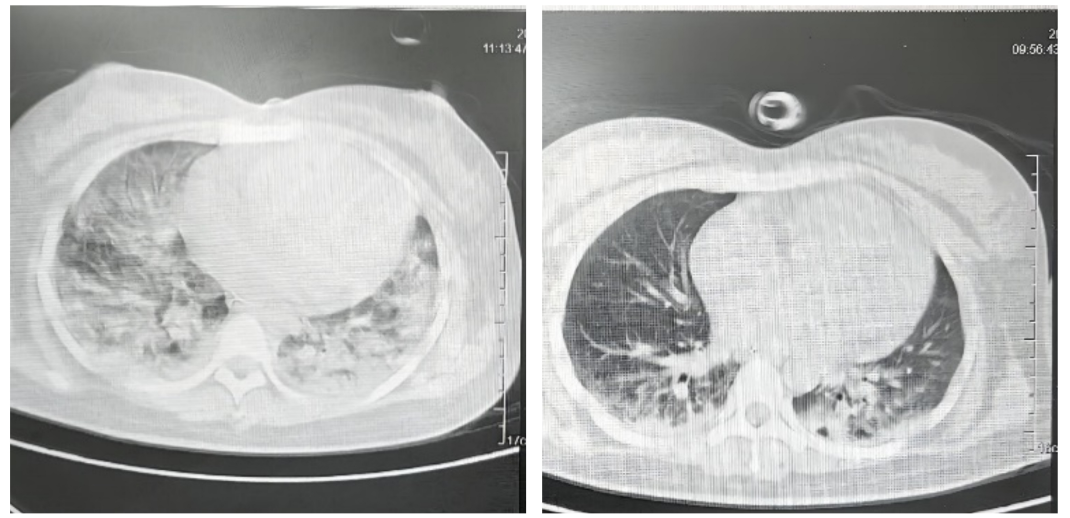

经过5天的治疗,患者肺部CT明显改善,由入院时满满的“大白肺”转变为“小白肺”,入院第6天,一只脚跨入鬼门关的患者顺利脱机拔管,于6月3日转回普通病房。目前,母子情况均良好。